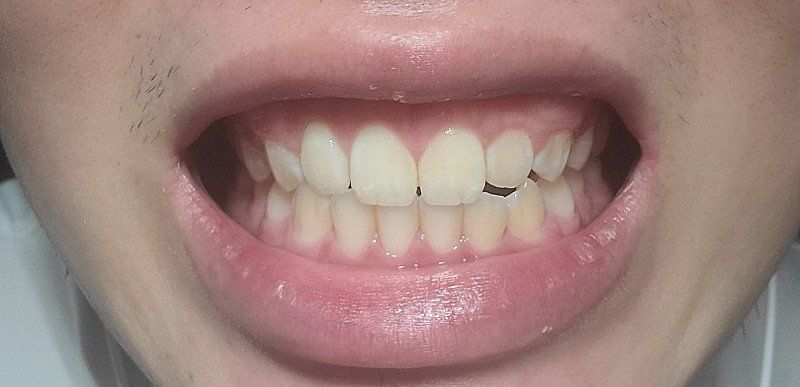

4. 치아 중심선이 윗니는 <- 방향 아랫니는 -> 방향으로 틀어진 턱 비대칭이 있는것 같아요 억지로 중심선 맞추면 치아교합부분이 이상해보여요 원래 이런가요? 인비절교정으로 교정가능한지?

정면사진

4. 치아 문제라기보다는 골격적인 부분이 동반되어 있어 교정을 하더라도 개선이 어려울 수 있으며 완전한 교정을 위해서는 양악 수술을 해야할 수 있어 보입니다. 턱 자체가 비대칭입니다.